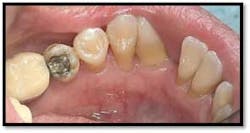

UL/LL reflected in a mirror and UL/LL radiograph